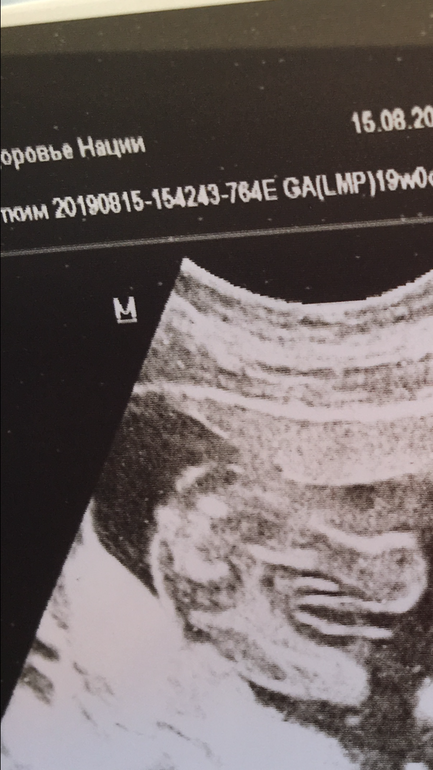

Сходили снова на узи в надежде узнать пол 🙈 кого видите?

Пол малышаМалыш опять засунул пуповину между ног, исполнял всё время кульбиты и врач со 100% так и не дала ответ. Но говорит, больше похоже на девочку 🤷🏻♀️ Писюн же сразу бы заметили на 19 неделях?

Щас девочку ждем, видно было с 22 уже, в 16, уже уверенно, в 20 ничего не поменялось, у вас тоже девочку вижу 😉

Пацанов обычно по яйкам высматривают 😁 На вашем сроке трудно было бы пацану своё хозяйство скрыть ☺️☺️☺️